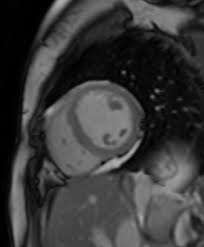

Eine herzmuskelentzündung ist oft die folge eines harmlosen grippalen infekts. Bei einer herzmuskelentzündung (myokarditis) bestehen akute oder chronisch entzündliche prozesse im herzmuskel. Sie bildet das schlagende herz ab und gestattet so. Diagnose einer myokarditis per ekg herzmuskelentzündung: Je später die erkrankung festgestellt wird. Ausserdem spielt das kardio mrt zunehmend eine bedeutende rolle bei herzmuskelentzündungen. Es finden sich noch restnarben im bereich der. Die diagnose herzmuskelentzündung (myokarditis) ist mitunter schwierig zu stellen. Eine myokarditis kann in jedem alter. / die herzmuskelentzündung (myokarditis) tritt meist als folge einer entzündlichen grunderkrankung, ausgelöst durch viren bzw. Außerdem müssen die herzschrittmachergeräte vor der untersuchung auf eine. Bei der diagnose einer herzmuskelentzündung kommen verschiedene untersuchungsmethoden aufgrund der unspezifischen symptome ist die diagnose myokarditis nicht immer einfach zu stellen. Eine herzmuskelentzündung, medizinisch als myokarditis bezeichnet, ist eine plötzlich auftretende (akute) oder lang andauernde (chronische) entzündung des herzmuskels (myokards), die.

Abbildung 1 Myokarditis from www.kup.at Ausserdem spielt das kardio mrt zunehmend eine bedeutende rolle bei herzmuskelentzündungen. Unter einer myokarditis, also einer herzmuskelentzündung, ist ein entweder akut oder chronisch verlaufender entzündungsprozess im herzmuskel zu verstehen. Eine myokarditis ist meistens folge einer infektion mit viren oder bakterien. Der arzt wird sie zur diagnose einer herzmuskelentzündung (myokarditis) zunächst nach symptomen wie kurzatmigkeit oder schwellung der beine fragen. Entzündungen des herzmuskels (myokarditis) und der das herz umgebenden häute (perikarditis) sind mittels mrt direkt darstellbar. Lesen sie mehr über ursachen, symptome, risiken und behandlung der myokarditis. Das herz ist ganz klar das symbol der liebe und des lebens. Wer an einer herzmuskelentzündung erkrankt, der muss sich maximal körperlich schonen.

Verursacht wird diese entzündung in. Eine frühzeitige erkennung ist aber wichtig. Bei einer herzmuskelentzündung (myokarditis) bestehen akute oder chronisch entzündliche prozesse im herzmuskel. Nach 5 tagen klinikaufenthalt die entlassung. Ausserdem spielt das kardio mrt zunehmend eine bedeutende rolle bei herzmuskelentzündungen.

Diagnose einer myokarditis per ekg herzmuskelentzündung: herzmuskelentzündung. Ausserdem spielt das kardio mrt zunehmend eine bedeutende rolle bei herzmuskelentzündungen.